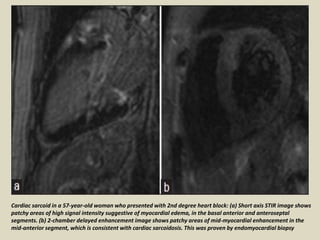

Cardiac sarcoid in a 57-year-old woman who presented with 2nd degree heart block: (a) Short axis STIR image shows

patchy areas of high signal intensity suggestive of myocardial edema, in the basal anterior and anteroseptal

segments. (b) 2-chamber delayed enhancement image shows patchy areas of mid-myocardial enhancement in the

mid-anterior segment, which is consistent with cardiac sarcoidosis. This was proven by endomyocardial biopsy